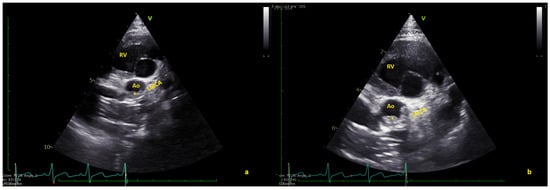

Figure 3.

(a) Long axis and (b) short axis views showing the complete thrombus resolution. Ao = native aorta; RV = right ventricle (Videos S3 and S4).